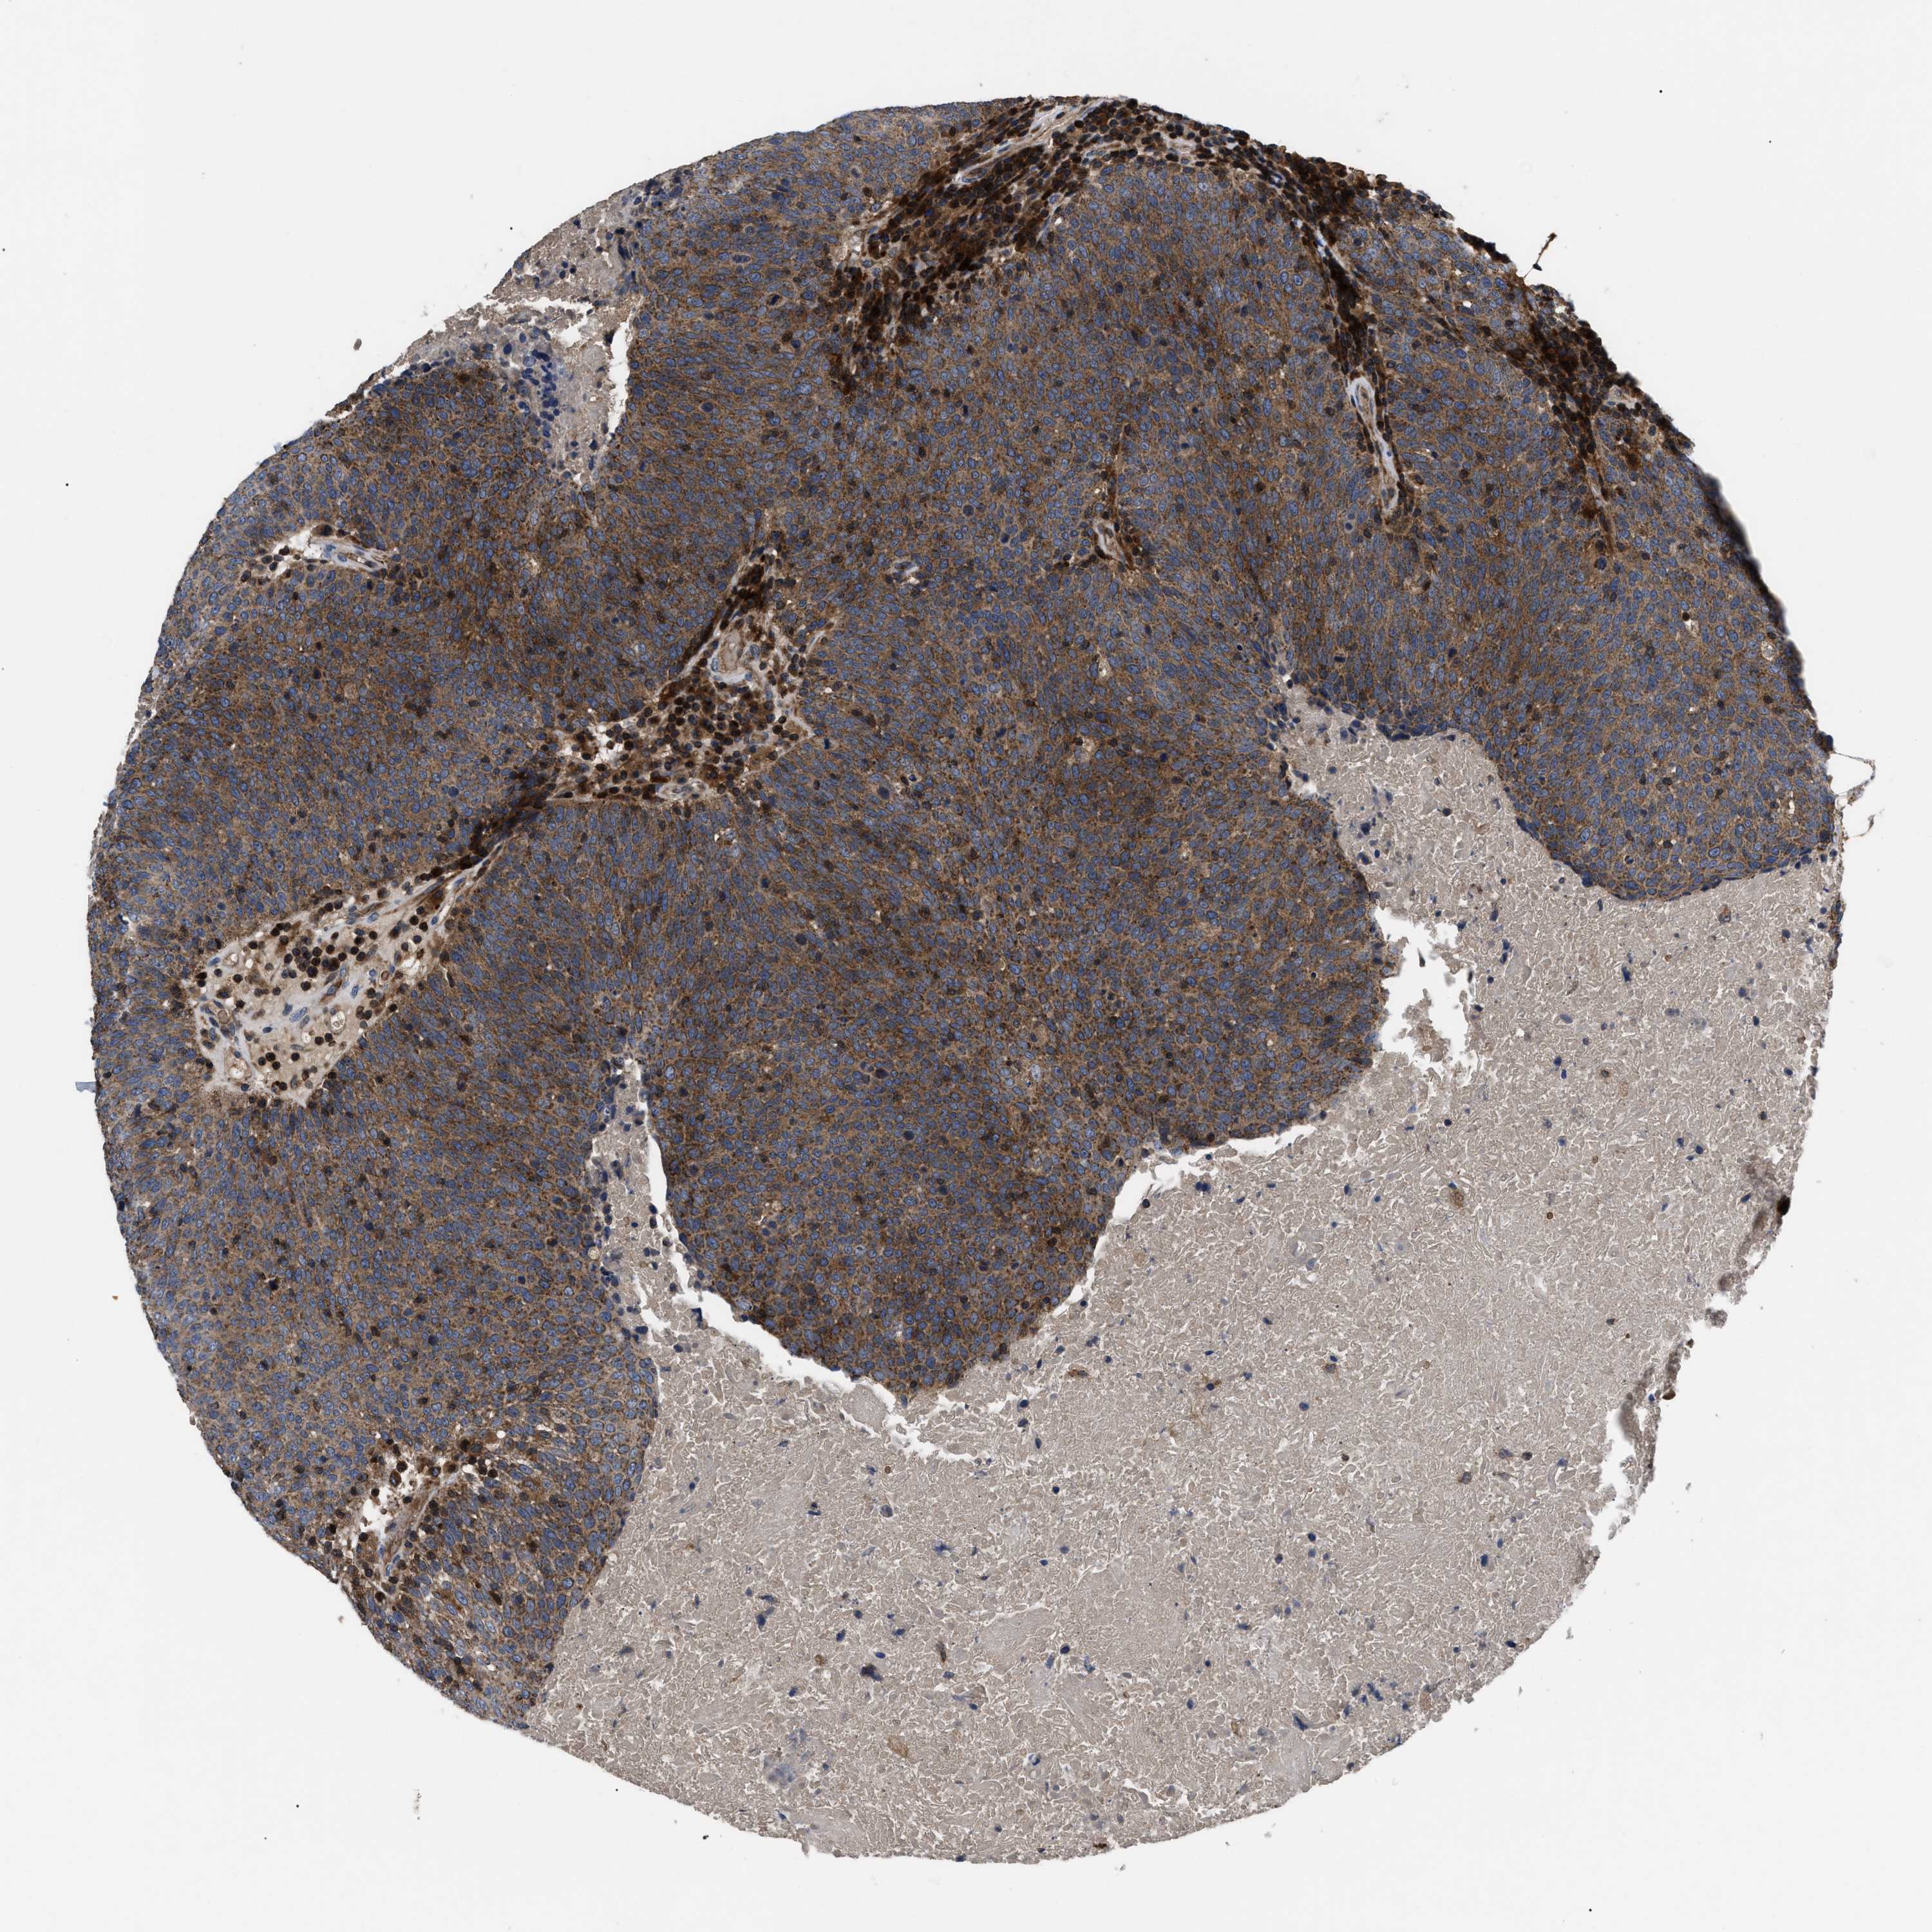

HEAD AND NECK CANCER - Protein expressioni

A mouse-over function shows sample information and annotation data. Click on an image to view it in a full screen mode. Samples can be filtered based on level of antibody staining by selecting one or several of the following categories: high, medium, low and not detected. The assay and annotation is described here.

Antibody stainingi

Antibody staining in the annotated cell types in the current human tissue is reported as not detected, low, medium, or high, based on conventional immunohistochemistry profiling in selected tissues. This score is based on the combination of the staining intensity and fraction of stained cells.

Each image is clickable and will lead to virtual microscopy that enables deeper exploration of all samples and also displays staining intensity scores, fraction scores and subcellular localization as well as patient and tissue information for each sample.

Antibody HPA018162

Staining

High

Medium

Low

Not detected

Intensity

Strong

Moderate

Weak

Negative

Quantity

>75%

75%-25%

<25%

None

Location

Nuclear

Cytoplasmic/membranous

Cytoplasmic/membranous,nuclear

Squamous cell carcinoma, NOS

Squamous cell carcinoma, metastatic, NOS

Adenocarcinoma, NOS